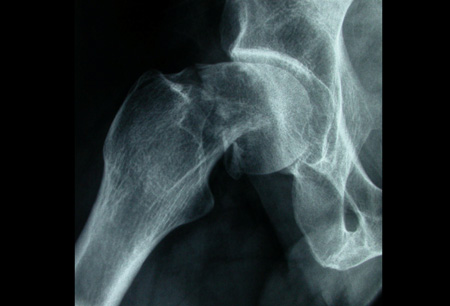

- radiografias simples